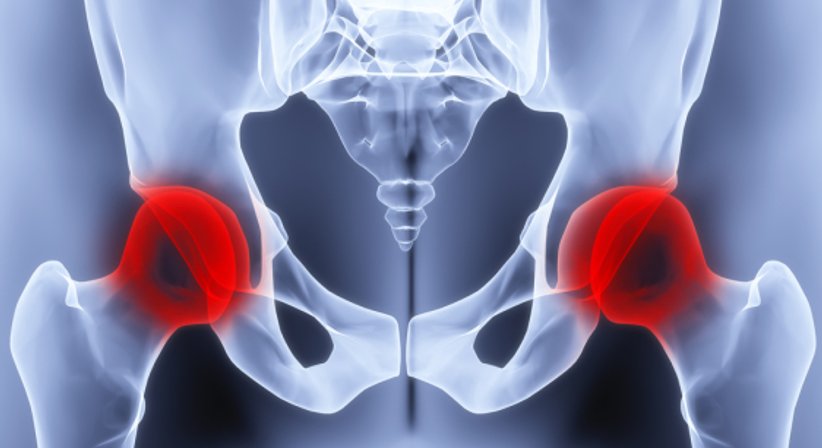

Coxarthrose / künstlicher Hüftgelenksersatz

Die Coxarthrose (Hüftgelenksabnüzung) zählt zu den häufigsten Arthrosen und betrifft überwiegend ältere Menschen. Es handelt sich um eine chronische Erkrankung vom Hüftgelenk, bei welcher es zu einem fortschreitenden Verlust vom Knorpel kommt. Mit Fortschreiten der Erkrankung gehen die Veränderungen auch auf die Gelenkkapsel und die angrenzenden Knochenenden über und es kommt zu einer Entzündung der Innenhaut vom Gelenk. Bei sehr fortgeschrittener Coxarthrose ist der Knorpel in der Hüfte soweit abgebaut, dass die Knochenenden schutzlos aneinander reiben.

Die Coxarthrose macht sich bei Betroffenen vor allem durch Schmerzen in der Hüfte und auch im Oberschenkel bemerkbar. Die Beschwerden treten zunächst nur gelegentlich auf, beispielsweise nach längeren Gehstrecken. Auch Einlaufschmerzen unter Belastung und Steifigkeitsgefühle sind typische Anzeichen einer Arthrose. Dazwischen liegen beschwerdefreie Intervalle, die mit Fortschreiten der Erkrankung jedoch immer kürzer werden. Weitere Symptome sind eine vorzeitige Ermüdung und eine eingeschränkte Beweglichkeit des Hüftgelenks mit begleitendem Hinken. Im fortgeschrittenen Stadium treten die Schmerzen auch immer häufiger in Ruhephasen auf.